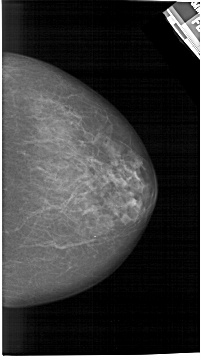

A_1455_1.RIGHT_MLO

RIGHT_MLO LINES 6556 PIXELS_PER_LINE 3886 BITS_PER_PIXEL 12 RESOLUTION 43.5 NON_OVERLAY